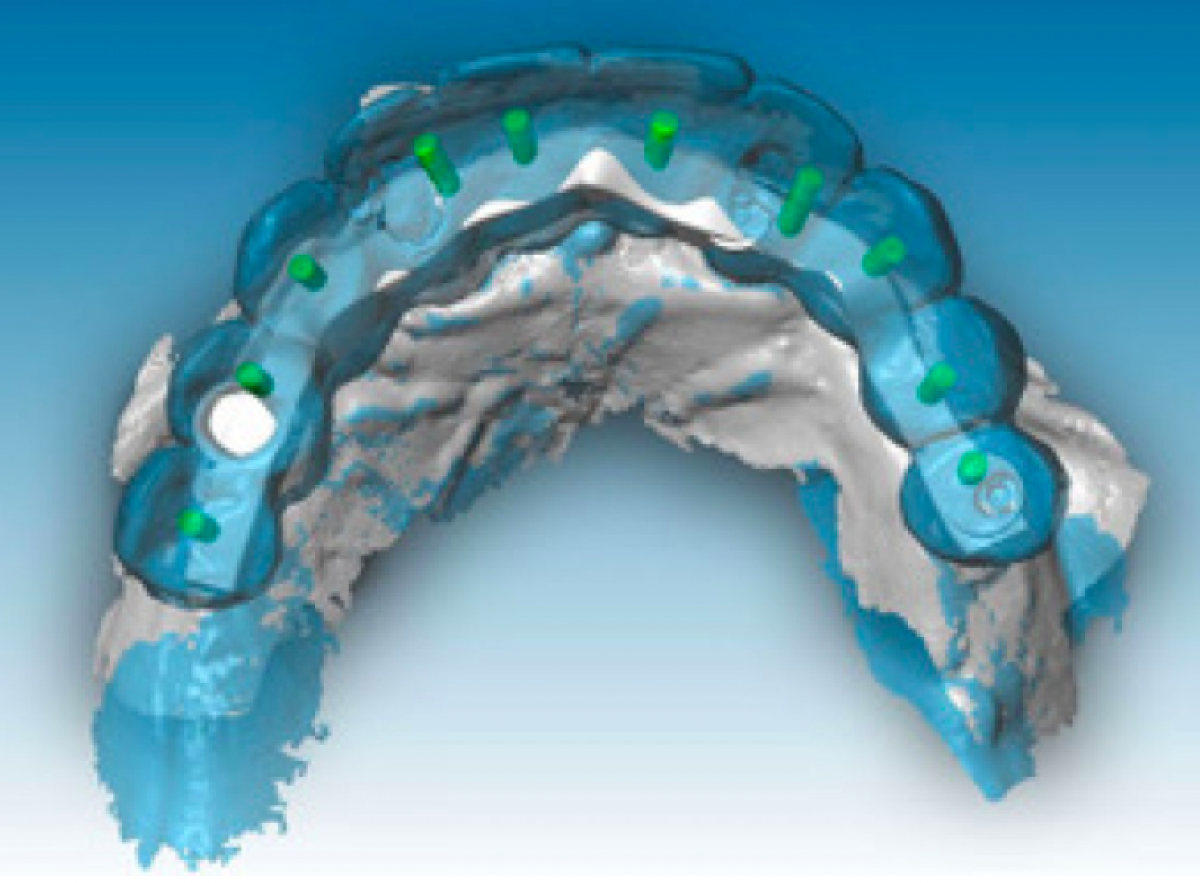

Thereafter, the provisionals were removed from the standard implants and scanbodies (Elos Medtech AB, Lidköping, Sweden) were screwed to the implants (Figure 2).

In this phase it is not possible to collect information about the occlusal relations between the two arches since there is no occlusal stop or stop. Finally, to collect the negative information about the soft tissues adjacent to the prostheses (implant emergence profile and gingival anatomy underlying the pontic elements), the upper and lower provisional were scanned outside the mouth and the third set of impressions ( STL3) was thus obtained. The three series of impressions STL1, STL2, STL3 were then imported into Geomagic Studio 12 software (3D Systems, Rock Hill, SC, USA) and combined using a specific automatic coupling algorithm. Since the gingival tissues scanned in the STL1 and STL3 series were the same, the software identified a good automatic coupling. Thereafter, the STL2 impressions were also coupled thanks to the correspondence between the form of the provisionals acquired in STL2 and STL3.Through the CAD union of the different fingerprints, a single file was obtained, called STL4, which contained the following information: three-dimensional scanbody position, soft tissue architecture, occlusal parameters and esthetic characteristics. The STL4 file was then imported into dental software (Dental Wings, Montréal, QC, Canada) to automatically and certify the position of the implants starting from the scanbodies (Figure 3).